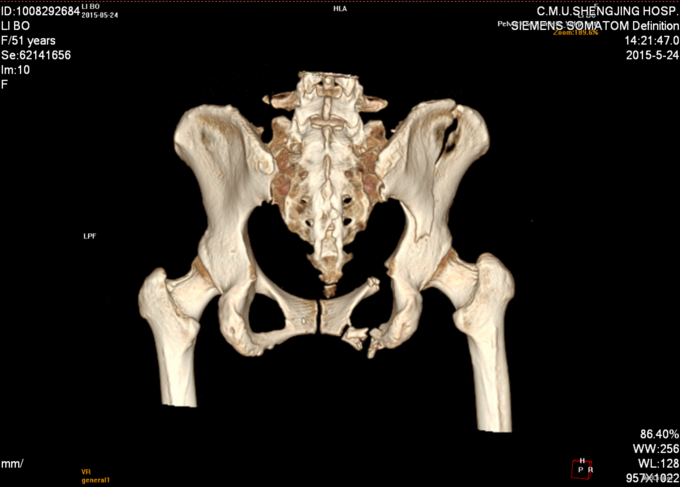

主诉:外伤后右髋部疼痛肿胀8天 现病史:患者于2015年5月16日发生车祸,伤后右髋部疼痛肿胀,下肢运动障碍,急诊120送至丹东市二医院,行骨盆平片,骨盆CT提示骨盆骨折,给予输血补液、骨牵引及留置尿管等对症治疗,急诊以“骨盆骨折”为主要诊断收入我科,患者病来无头晕头痛,无恶心呕吐,留置导尿中,大便正常。

诊断:骨盆骨折(Tile B1) 患者入院后完善检查后,全麻下行骨盆骨折切开复位钢板内固定术,术后给予抗炎,消肿,冷敷,患肢抬高等对症治疗。患者每天换药观察切口愈合情况,无红肿及渗出,待伤口14天后予以拆线治疗,予以出院,给予康复处方。